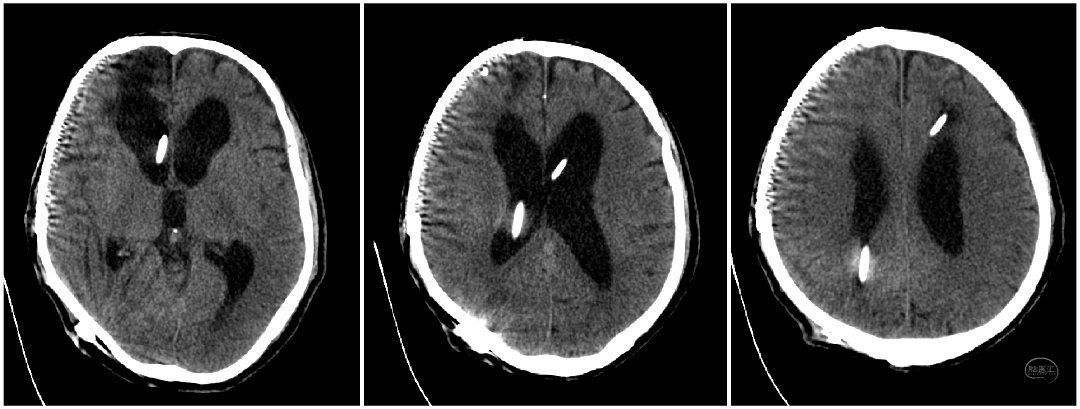

目前低颅压性脑积水的病理生理机制仍未明确,有学者提出黏弹性原理,在脑积水形成初始,脑室内脑脊液积聚使脑室内压力增大,使脑组织这个黏弹性体受力逐渐变形,脑室形态不断扩大,当扩大到一定程度后脑室内压力下降,类似施加在黏弹体上的压力被卸载,因黏弹体变形恢复存在滞后延迟效应,此时脑室内虽然已呈低压状态,但扩大变形的脑室未能同步恢复正常。目前研究主要倾向于LPH与脑顺应性的改变有关。对于确诊LPH的患者,除积极处理病因外,还可采用持续的脑室低压或负压外引流,其目的在于降低直至消除侧脑室-蛛网膜下腔的压力梯度差,逐渐恢复脑组织弹性,促进脑室形态和脑组织顺应性恢复正常。住院期间对该患者间断Ommaya囊抽取脑脊液1次/日,60-70ml/次,患者智力减退、步态不稳等症状无明显改善。后期调整Ommaya囊抽取脑脊液次数,改为2次/日,80-90ml/次。在增加脑脊液抽吸量及频次后,患者意识及智力减退症状逐渐好转,可逐步经口进食。

针对低颅压脑积水最常用的治疗方法为脑室-腹腔分流术。进行治疗过程中分流管的选择对于患者的预后质量具有重要影响,分流不足与分流过度均会造成严重并发症,不仅影响治疗效果,甚至会导致患者死亡。谢国强主任组织科室研究讨论制定治疗方案。患者脑脊液指标正常后,计划行脑室腹腔分流术。本次选用ProSA+ProGAV系统可调压式分流管为是西北地区首例。proSA是首个允许在直立位,以及在直立位与仰卧位见的任何角度进行开启压力调节的脑积水阀门,其开启压力随患者体位变化而改变。当处于水平体位时,重力装置无阻力,仅压差装置决定整个分流系统的开启压力。处于直立体位时,完整分流系统的开启压力为压差装置开启压力和重力装置开启压力之和。应根据患者身高、体重和年龄选择重力装置的开启压力。它为各种类型的脑积水提供了更多的治疗选项和可能性,大大超越了传统可调压分流管的局限。抗虹吸(抗静水压压力)大小设置可以从0—40cmH2O,适应每位患者的个性化需要。proGAV 因其使用了重力智控阀,其在仰卧位时处于未激活状态,站立位时重力智控阀与可调压阀协同工作,阀门整体开启压力增加,有效的保护了患者避免受到过度引流的影响。proSA可以与不同类型的压差阀组合使用,21级抗虹吸档位可选,与proGAV联合使用可提供高达21*21=441种压力组合。根据患者体位自适应所需开启压力。钛合金的外壳确保高可靠性,避免了外界压力及皮下压力对阀门的影响。手术在脑室镜及腹腔镜辅助下进行,有助于准确定位相应解剖结构,将分流管置于比较理想的位置,从而降低管道被堵塞的机会。术后复查头颅CT可见(脑室较前缩小,间质水肿减轻明显)。